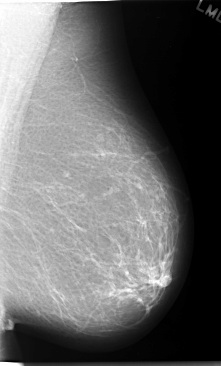

C_0057_1.LEFT_MLO

C_0057_1.LEFT_CC

LEFT_MLO LINES 5848 PIXELS_PER_LINE 3536 BITS_PER_PIXEL 12 RESOLUTION 50 NON_OVERLAY